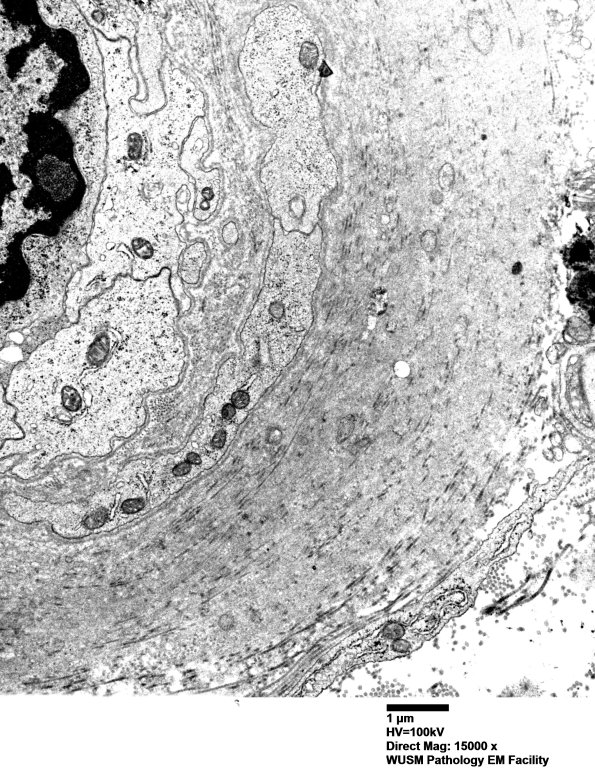

Washington University Experience | VASCULAR | Hypoxia-Ischemia, fetal-neonatal | White Matter | 5C2 (Case 5) EM016 - Copy

5C2 (Case 5) EM016 - Copy